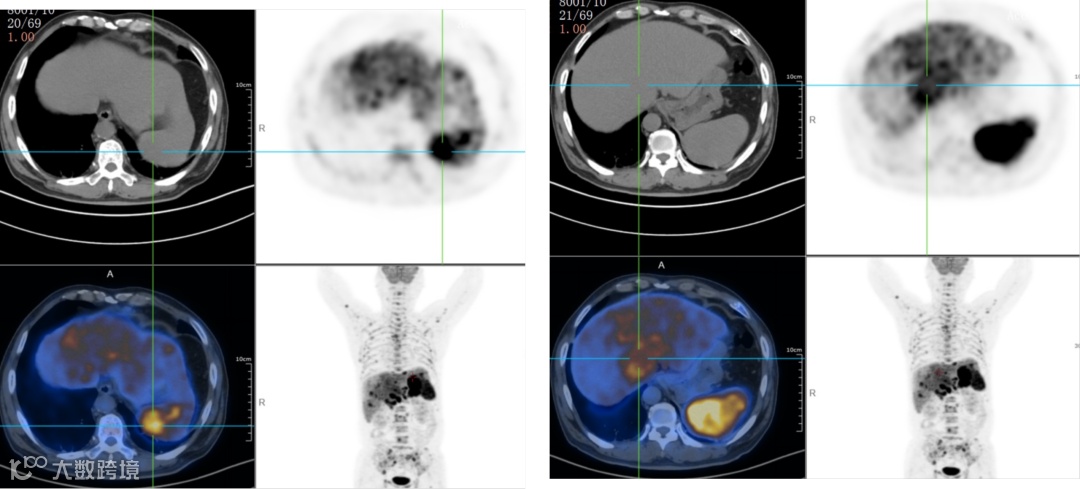

双侧内乳区、膈上、右侧膈肌脚区、肝门区、肝胃间隙、脾门区、腹膜后多发淋巴结,肝脾肿大,代谢增高;脊柱多个椎体及部分附件、双侧肱骨、双侧肩胛骨、双侧锁骨、双侧多根肋骨、胸骨、骨盆诸组成骨、双侧股骨上段多发代谢异常增高灶。